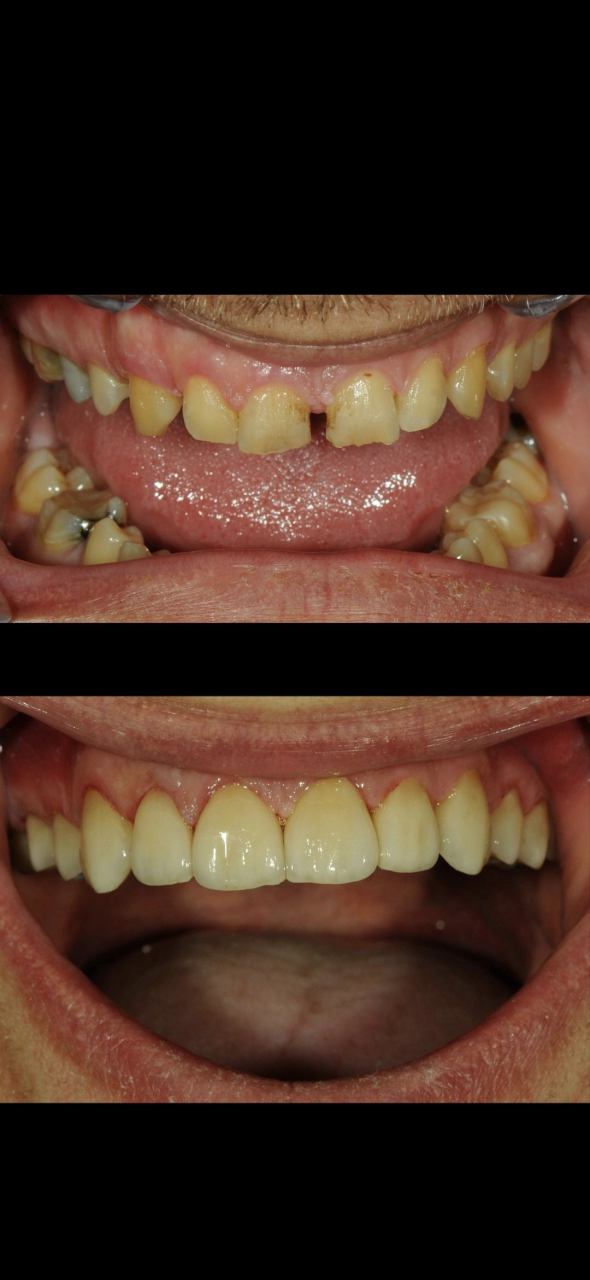

Estetska stomatologija

Estetska stomatologija obuhvaća niz zahvata koji imaju za cilj poboljšanje izgleda zubi, osmijeha i općenito estetike usne šupljine, uz očuvanje ili poboljšanje funkcionalnosti.

U Microdentalu se možete naručiti na različite tetmane i zahvate: izbjeljivanje, korekcija oblika zuba, zamjena starih ispuna ili kompletan smile makeover.

LJUSKICE

Keramičke ljuskice (veneers) predstavljaju idealno rješenje za estetske korekcije prednjih zuba. Može se korigirati oblik zuba, boja, veličina i sitne nepravilnosti u položaju.

Ljuskice se izrađuju potpuno individualizirano, uz pomoć digitalne tehnologije i u vlastitom laboratoriju. Za dodatne informacije ili dogovor oko termina nazovite ili pošaljite upit

Smile design

Digitalno planiranje novog osmjeha. Unaprijed se kompjuterski određuje oblik, boja, dužina zuba te definitivni izgled pacijenta.